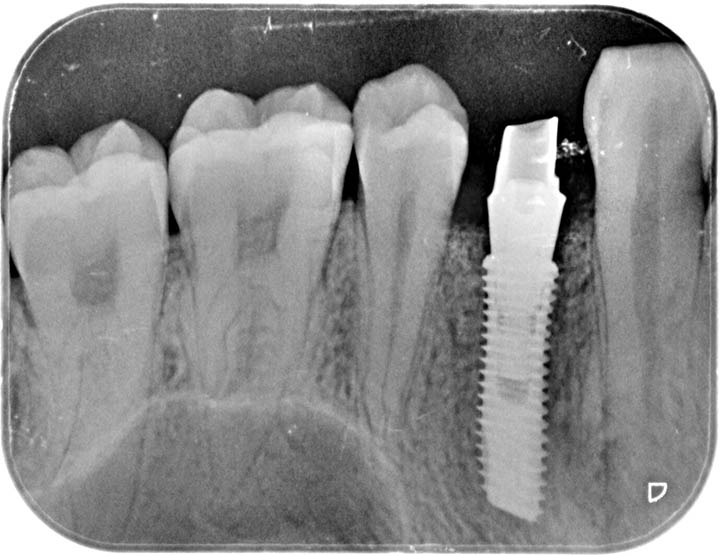

全景CT片,可明显看到右上第一磨牙缺失

局部麻醉后对缺失牙进行登腾种植体植入修复手术,术中发现颊侧骨壁缺损。

将种植体植入后,颊侧缺损骨壁植入骨粉,加固种植体。

将登腾种植体旋入愈合基台

完成种植体植入,6个月后复诊进行冠修复

种植牙修复后,种植体与牙槽骨紧密结合,种植牙与真牙外观极其相似,上下牙咬合正常,种植体周边无骨吸收情况,效果非常好